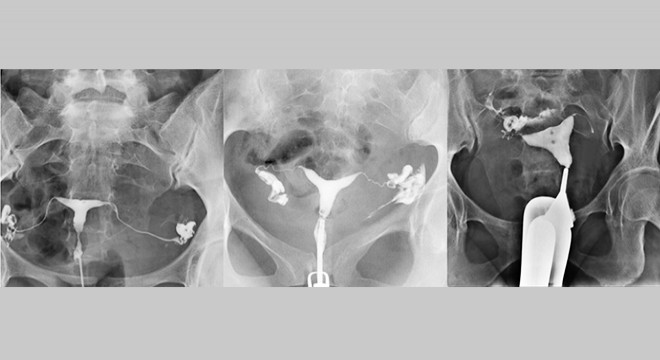

Rahim filmi diğer bir ismi ile HSG, rahim boşluğunu görüntüleme de kullanılan bir tanı yöntemidir. Bu yöntemde; rahimdeki tüplerde olabilecek tıkanıklık, genişleme ve darlık gibi problemler tespit edilir.

Rahim filmindeki amaç; rahmin şekli, boşluğu ile ilgili kalıtsallıktan kaynaklı problemler veya polip-myom gibi sonradan gelişim gösteren ve kısırlığa yol açabilecek problemlerin tespiti, özellikle düşük- kürtajdan sonra çok sık görülen yapışıklıkların saptanmasıdır.

Görüntüleme yöntemi ayrıca tüp bebek ya da aşılama tedavisine başlanmadan önce de yapılmaktadır. Rahim içindeki tüplerin ve boşluğun kontrast madde verilip radyografik yöntemler ile incelenmesi sağlanır. Tıbbın geliştirdiği teknolojik cihazlarla bu rahim filmi acısız ve ağrısız bir şekilde çekilebilir.

İşlem esnasında görüntüleme cihazındaki ortaya çıkan sıvı, rahmin ağız kısmından içerisine verilerek; bu sıvının, rahmin içerisini ve tüpleri görünür duruma getirmesi sağlanmaktadır. Sıvı genel de içinde iyot tuzu bulunan bir sudur. İyot, X ışınlarını tutma konusunda sorumludur. Böylelikle rahmin içi ve tüplerden görüntü alınabilir. Kokusu bulunmaz ve rengi de olmayan bir sıvıdır. Yakıcı değildir.

İşlemdeki kontrast madde; rahmin ağız kısmından basınçla verildiğinden, bazı durumlarda tüplerdeki mukus vb. engelleyici yapıları temizleyip tedavi edici etkisi bulunmaktadır. Uygulama en çok 15 dakika da tamamlanmaktadır. Rahim filmi işleminden sonra hastalar, günlük yaşamlarına etki edecek herhangi bir hastalık hissetmezler. İşlemden sonra hafif seviyede görülen sızıntı şeklindeki kanama, normal olarak kabul edilir.